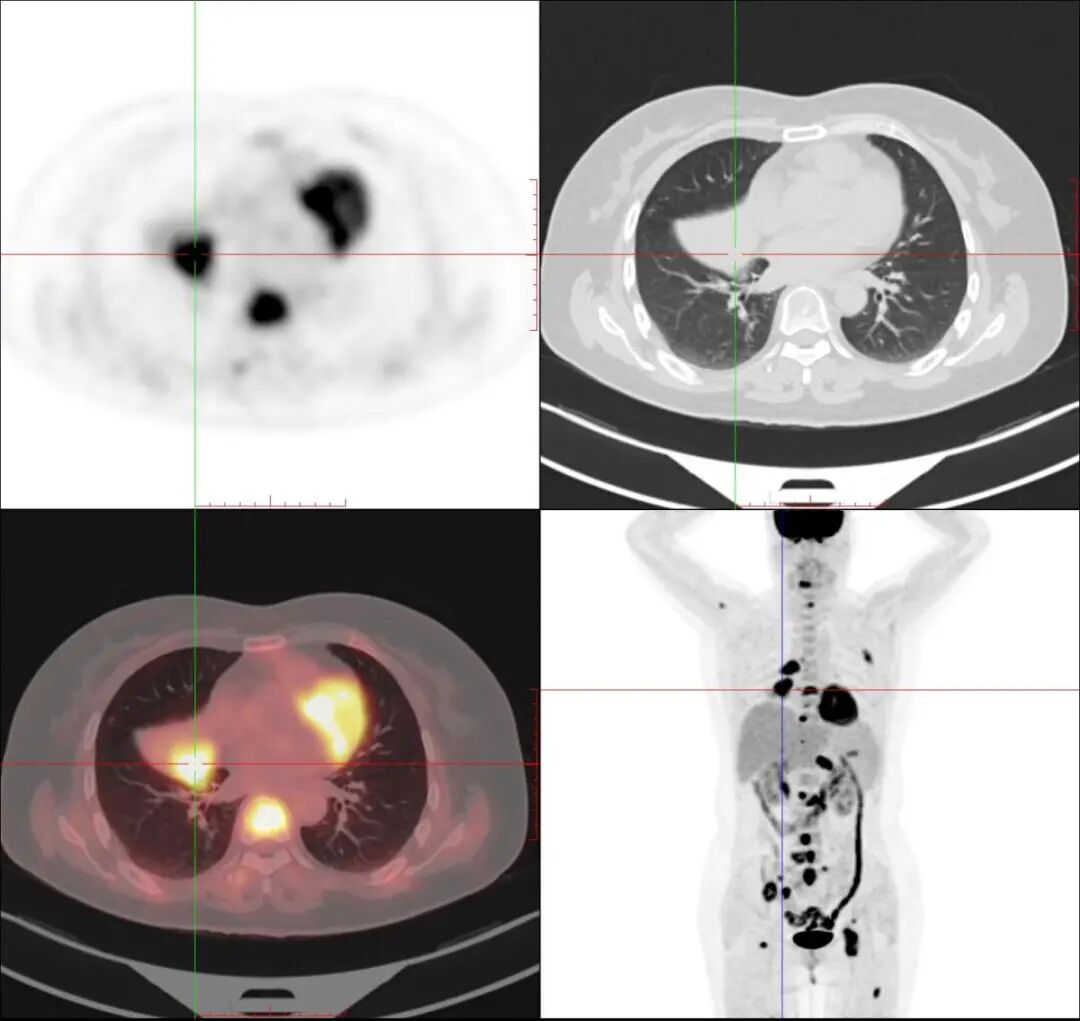

女性,37岁,左乳癌术后转移再分期。

显示纵隔、双肺门、左上胸壁转移灶部位多个异常代谢明显增高区。